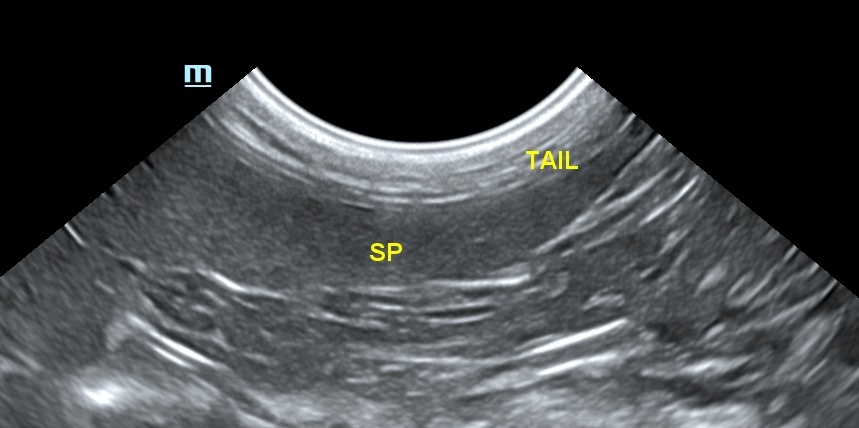

스캔 시 비장의 모양은 혀(tongue) 모양을 가지며, 꼬리부분이 머리 부분과 몸통보다 넓습니다. 횡단면은 삼각형 모양으로 개의 비장보다 작으며, 위치가 일정합니다. 비장의 머리 부분은 위비장 인대에 의해서 위에 고정되어 있으며, 몸통과 꼬리는 많은 유동성이 있으나, 그 유동성의 정도는 개보다 적습니다. 건강한 고양이에서 비장은 얇고, 고에코성의 캡슐표면으로 부드러운 모양으로 잘 확인이 되며, 깨끗한 경계 부위를 가집니다. 비장의 실질은 치밀하고 동질성의 미세한 과립성의 echotexture를 가집니다(그림 2).

비장의 측정에서 가장 신뢰할 만한 것은 비장의 머리부분을 재는 것이었습니다. 그러나 최근 권장된 최종 프로토콜에는 혈관이 내장 표면에 보일 때 횡단면에서 비장의 근위 1/3 높이를 측정하는 것을 추천합니다.4) 이때 5.1~9.1mm가 되며, 9.1mm 초과 시에는 비장의 비대를 뜻합니다(표 1).